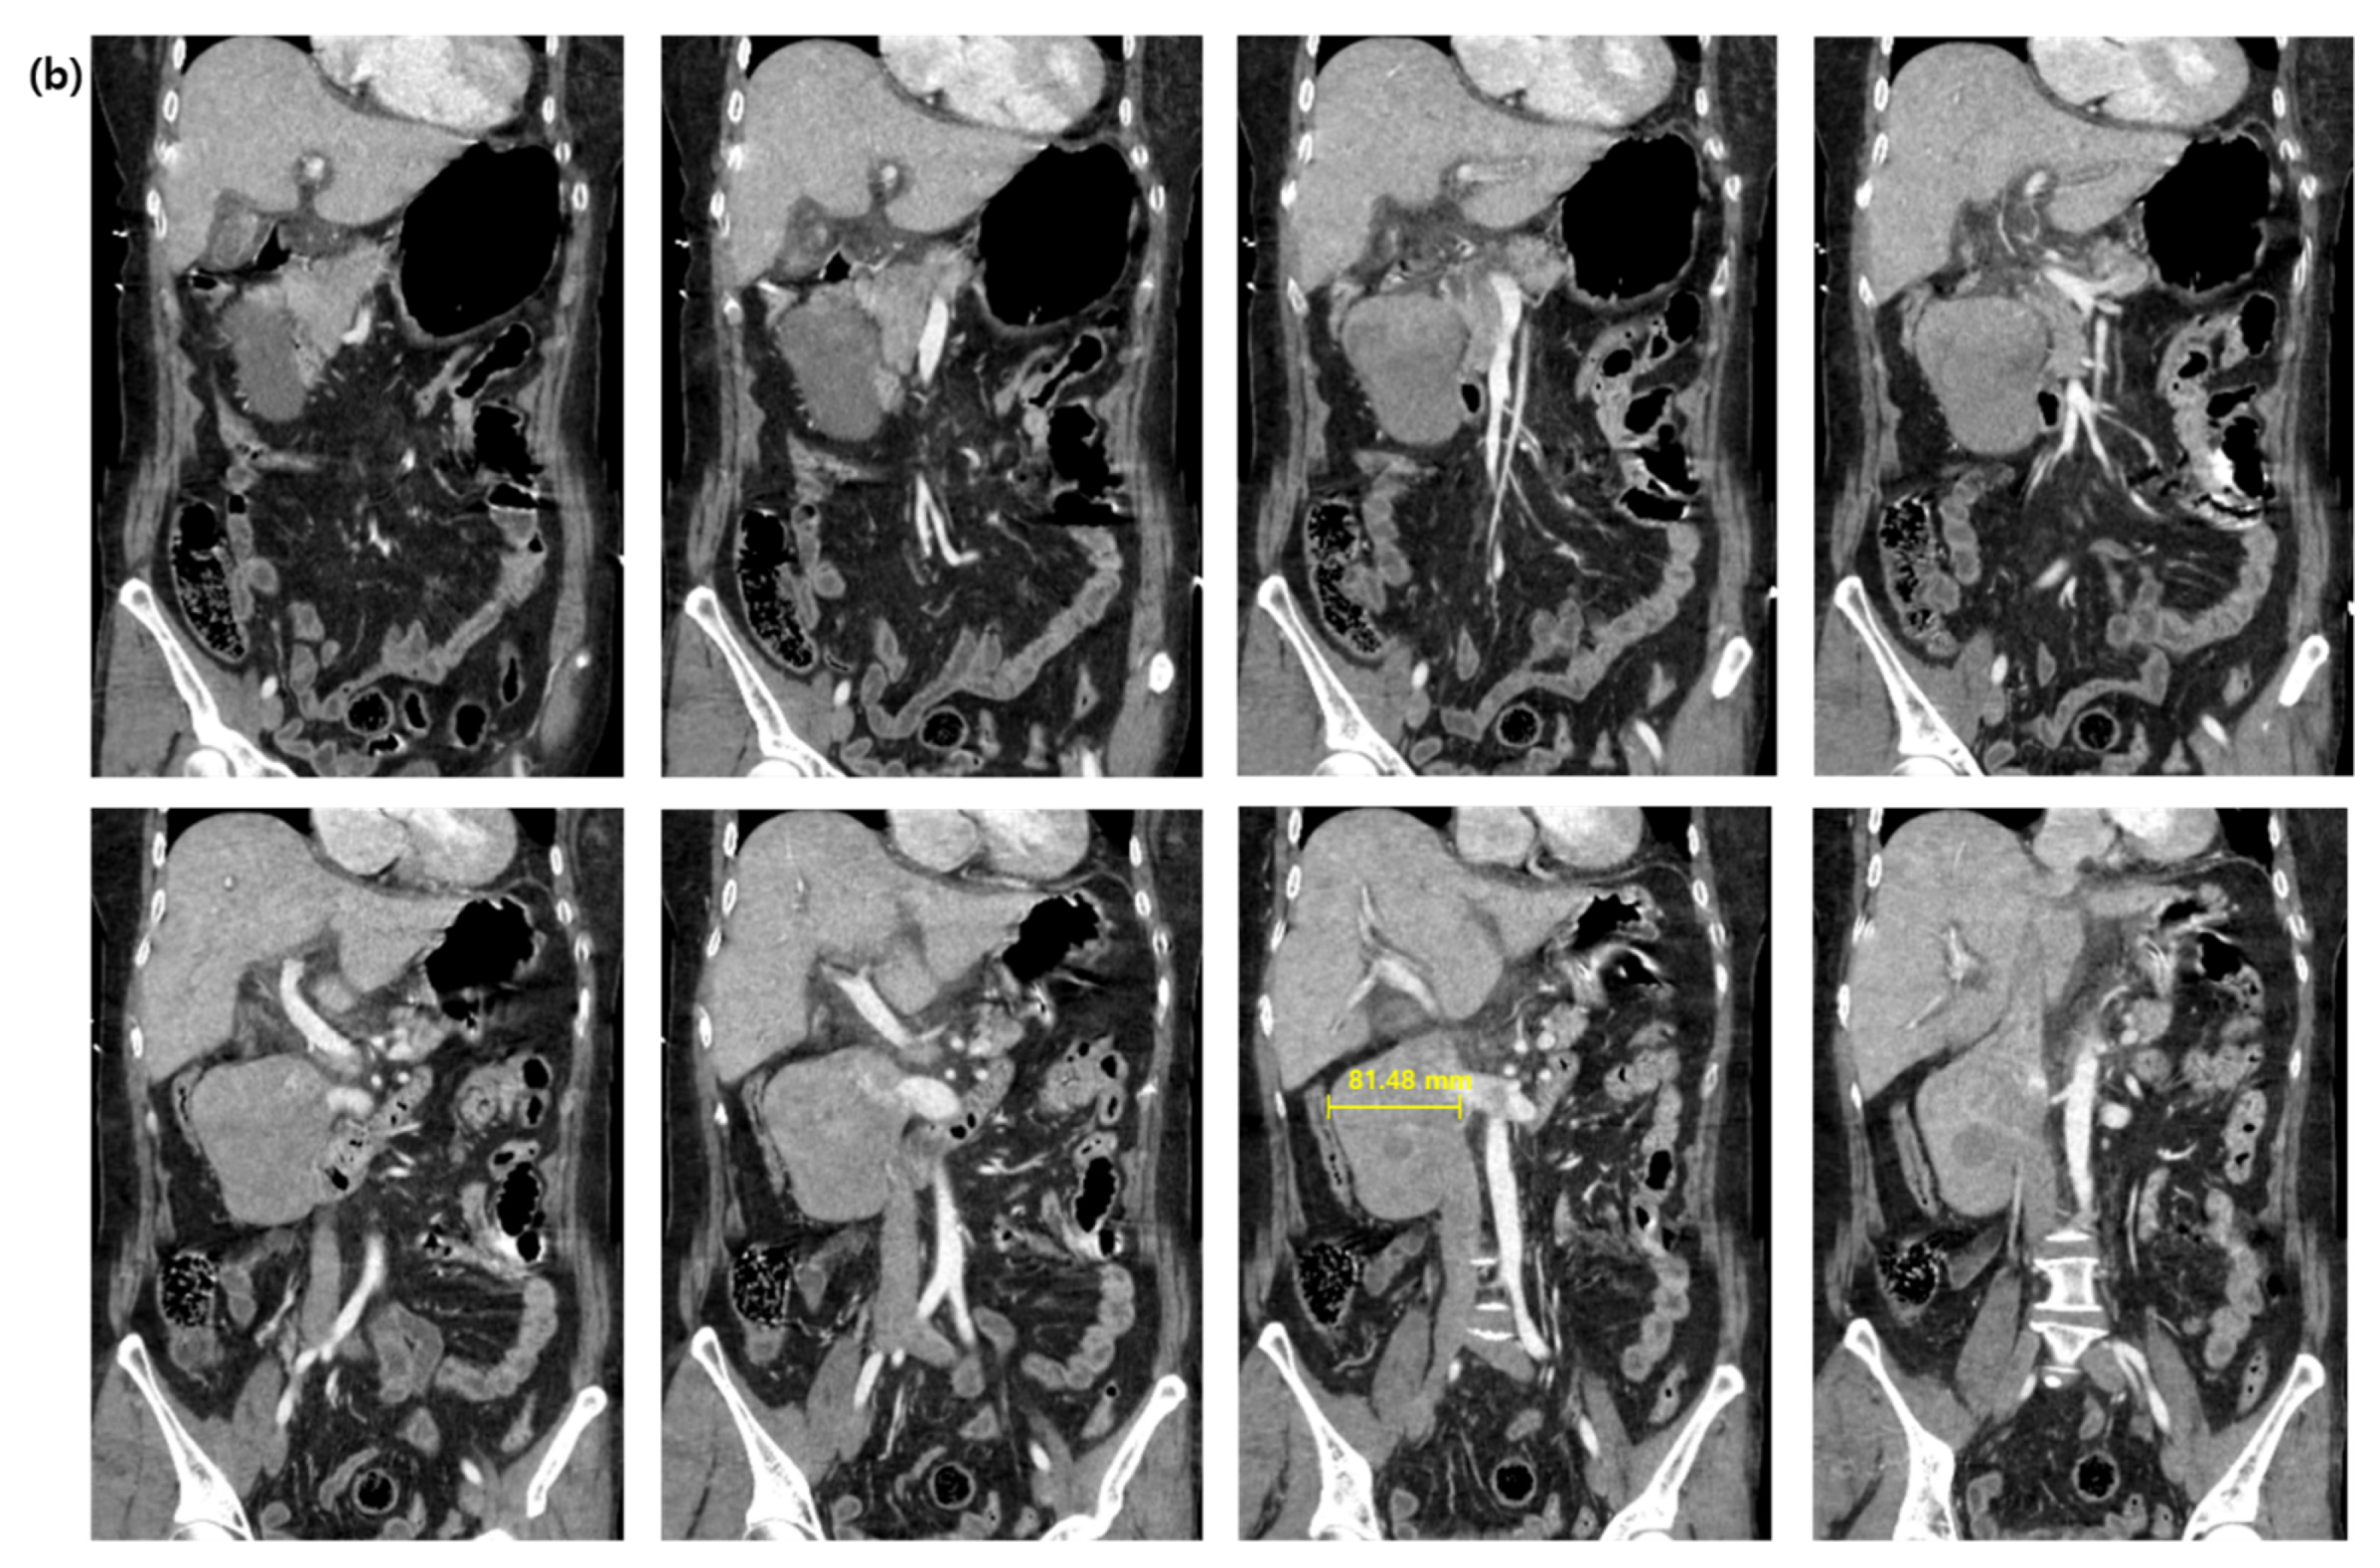

2. Case Presentation